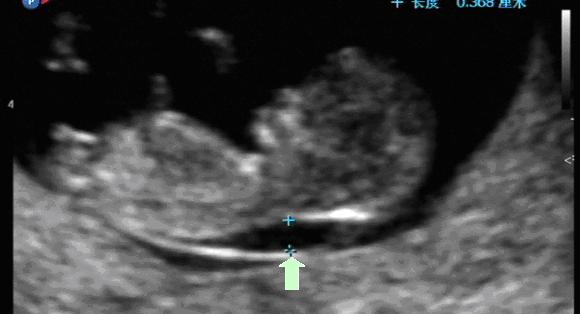

图5:NT正常的胎儿(箭头所指处即为NT) 图6:NT增厚的胎儿(箭头所指处即为NT)

在孕11-14周期间,绝大多数正常胎儿的NT值都在3mm以下,如果这个值超过3mm,就可怀疑胎儿有异常,但是也不能仅凭NT增厚就确诊胎儿唐氏综合症,还需要进一步进行排畸检查。排畸检查可能是羊水穿刺或是无创产前基因检测,这两者的准确性高,但价格相对较贵,还不适于普遍筛查。